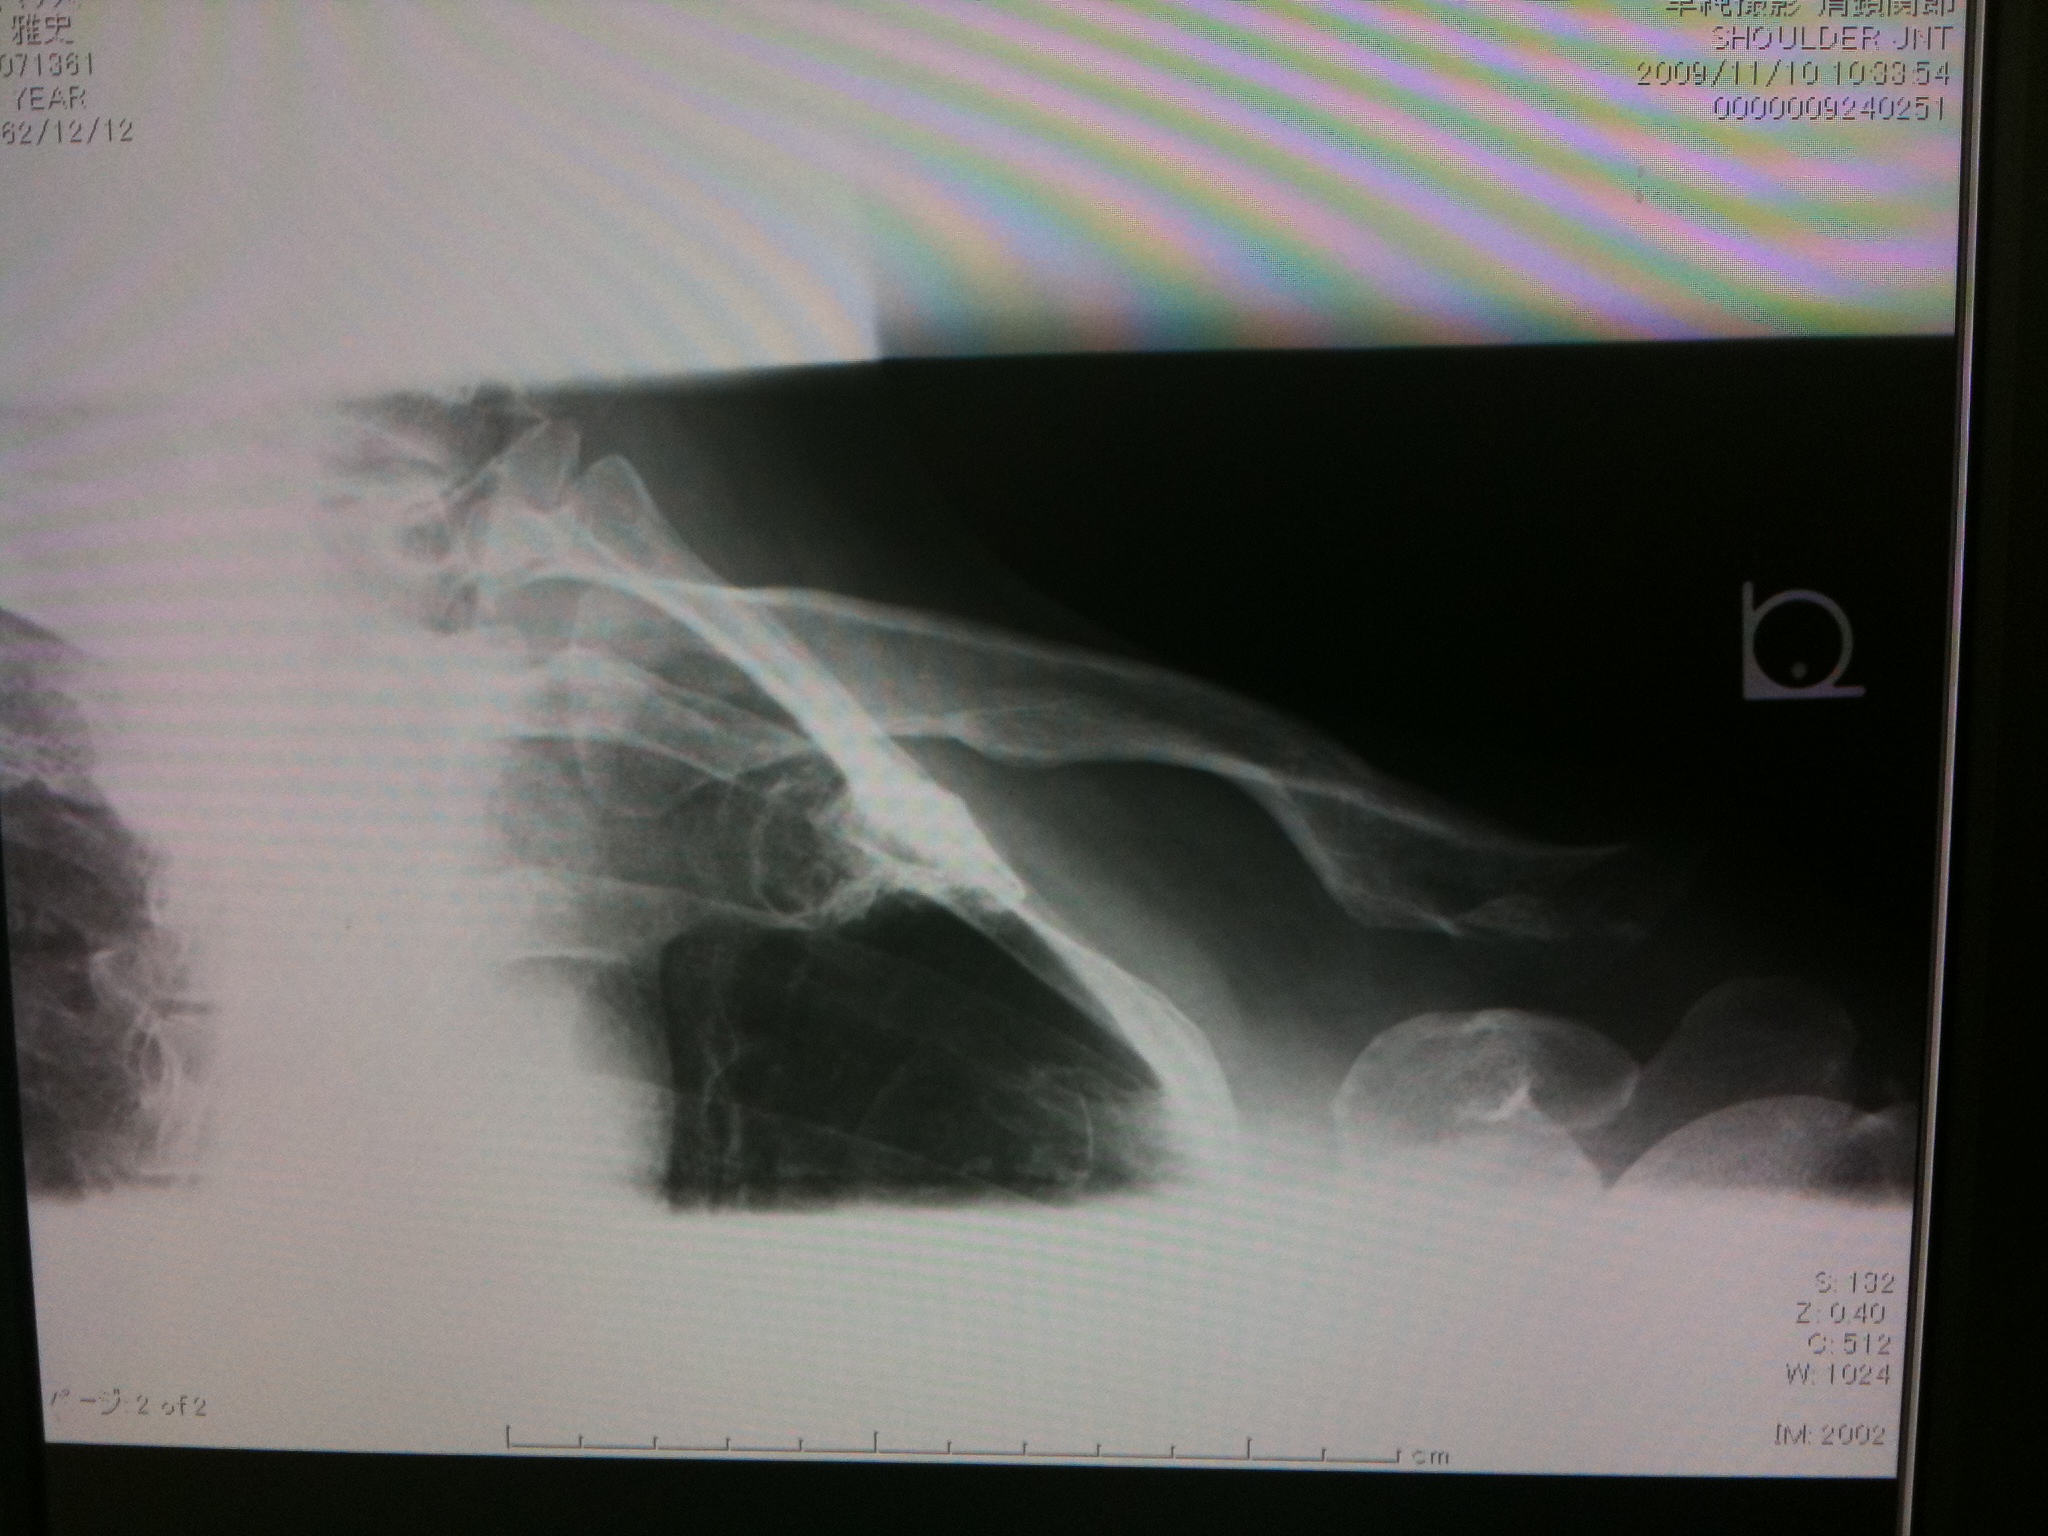

この角度だとよくわからないのですが、外れた骨の下にやはり白い影が見えます。でも痛みはなくて、三角巾は外しています。